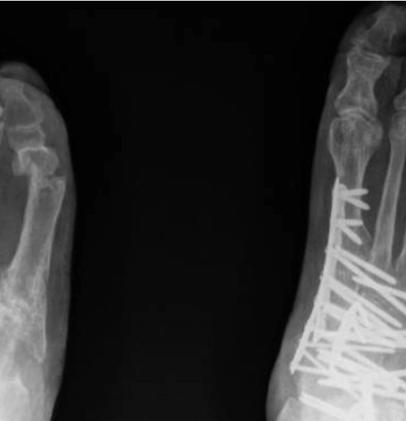

4fordatacollectiontools.)Thrombotic eventswerecollectedduringindexhospitalizationandat30 and90daysafterdischarge.Wedefinedthromboticeventsas deepveinthrombosis(DVT),pulmonaryembolism(PE), ischemicstroke,myocardialinfarction,orotherarterialor venousthromboembolicevents.Doortoneedletimewas definedastimefromhospitalpresentationtoreceiptof reversalagent.OnsettoCTtimewascalculatedusingthe differencebetweeninitialCTandtimeofbleedingonset, wheretheybothexisted;onsettoCTtimefortheremainder ofcaseswasdeterminedbycombiningcategoricalonsetto presentationtime(<6,6–12,12–24,24–48,and >48hours),

usingthemediantimeforeachcategory,withdoortoCT time.Wedefinedallstudydataandvariablespriorto initiatingthestudyandtrainedourdataabstractorsusinga libraryofdefinitions(see Supplement1).Weperiodically monitoreddatacollectionandprovidedfeedbacktothedata abstractorsduringandafterdatacollectionandentry regardingmissing,conflicting,orobviouslyerroneousdata. Thenumberofdataabstractorsateachinstitutionvaried from1–3.Thedataabstracterswerenotblindedtotherapy.

Outcomes

Wedevelopedallstudyoutcomesapriori.Theprimary outcomeswerepresenceofestimatedtimesfromlastdoseof FXa-Iandtimefrombleedingonsettoadministrationof 4F-PCCorandexanetalfa.Secondaryoutcomeswere hemostaticefficacyasdefinedbytheANEXXA-4criteria,23 survivaltohospitaldischarge,thromboticeventsduringthe indexhospitalizationandat30and90days,andrebleeding eventssuchasICH,rectalbleeding,melena,orhematemesis.

DataAnalysis

Weuseddescriptivestatisticstosummarizethedata. Categoricaldataarepresentedasnumbersorpercentages andcomparedbetweengroupsusingchi-squareorFisher exacttestsasappropriate.Continuousvariablesare presentedwithmeansandstandarddeviationsormedians andinterquartileranges(IQR)basedontheirdistribution andcomparedwith t -testsortheMann-WhitneyUtests,as appropriate.Becausethiswasapilotstudy,noformalsample sizecalculationwasperformed.Wechosetoinclude25 patientsineachofthefourstudysubgroups:ICHtreated withandexanetalfa;ICHtreatedwith4F-PCC;GIBtreated withandexanetalfa,andGIBtreatedwith4F-PCC.An exploratoryPSMmodelwasconstructedtoestimatetheodds ofexcellent/goodhemostaticefficacyinpatientstreatedwith andexanetalfaor4F-PCCadjustingforage,gender, comorbidities,timefromlastdoseofFXa-I,time frombleedonsettotreatment,andindication foranticoagulation.